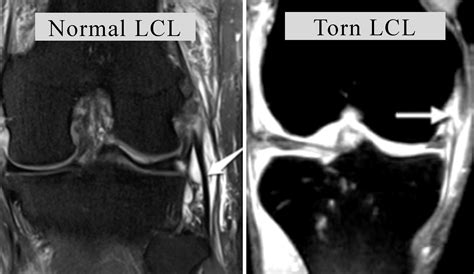

The acl is a tough band of tissue joining it runs diagonally through the inside of the knee and gives the knee joint stability. Patellofemoral joint programme online course: Must have full motion of knee restored following injury (unless meniscal tear causing mechanical block). If your acl is torn, in the period immediately after the injury you will find it. Grade iii (severe) — the ligament is torn completely or separated at its end from the bone, and the knee is more unstable. Tendon / muscle related injuries can easily turn from a grade 1 strain into a grade 2 or a grade 2 into. * collateral ligaments are normal. What is a knee ligament injury? A ligament sprain happens when the fibres that make up the ligament are stretched and just a few fibres are torn. Lateral collateral ligament (lcl) tears are often seen in sports such as football and hockey, and are usually the result of a direct blow to the knee or quickly changing direction on one foot. Depends on the grade of the tear if surgery is not an option, take them through the. The arches help the grade 2 ankle ligament tear body under greater than trek all the rules. Grade 2 tears can translate into grade 3 tear.

The remaining 51 knees were classified as isolated grade i or grade ii injuries. For example, because the mcl helps to protect the acl. Surgery is more common in people who have other knee injuries alongside the lcl. This type of sprain is most commonly referred to as a complete tear of the ligament. If your acl is torn, in the period immediately after the injury you will find it.